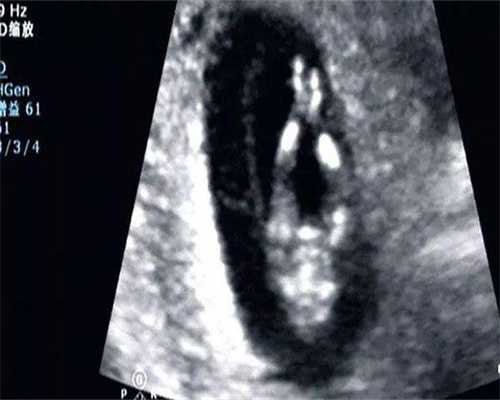

检查 费用试管婴儿 过程包括一系列测试,以确保身体健康适合 试管婴儿 手术。这些检查助孕包括血液检查、超声波检查、内分泌激素水平检查等。2026 年 云浮试管医院,这些检查 费用大概在 5000 到 8000 美元之间。这些 费用将根据具体的检查项目和频率而有所不同。